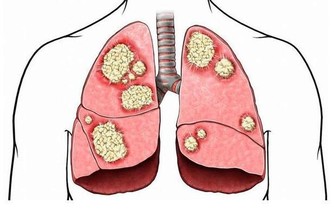

三是非口源性口臭:和前兩個相比,非口源性口臭最危險,因為它可能是體內各種器官病變引起的。例如咽炎、胃炎、胃潰瘍、便秘、尿毒症、肝腎功能衰竭等疾病。

幽門螺桿菌:經口腔進入人體,是目前所知能夠在人胃中生存的唯一微生物種類。幽門螺旋桿菌病包括由幽門螺旋桿菌感染引起的胃炎、消化道潰瘍、淋巴增生性胃淋巴瘤等。幽門螺旋桿菌病的不良預後是胃癌。

幽門螺桿菌它會引起胃黏膜輕微的慢性發炎,甚或導致胃及十二指腸潰瘍與胃癌。